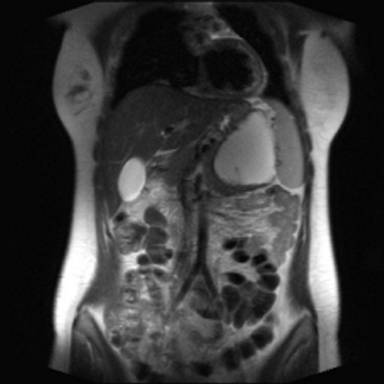

Abdominal US revealed an 8 cm anechogenic mass in the pancreatic tail. Abdominal CT scan was performed using a multi-detector 64 slices CT scanner (Aquilion, Toshiba, Tochigi, Japan) to confirm US findings; unenhanced CT scans showed a well-circumscribed cystic lesion, measuring 8x10 cm in pancreatic tail, with homogeneous low density; an internal this septum was present within the lesions. A contrast-enhanced acquisition was subsequently performed after i.v. bolus (3 mL/sec) injection of 120 mL of a non ionic iodinated contrast agent (Ultravist 370 mgI/mL, Bayer-Shering Pharma, Berlin, Germany) with a scan delay of 120 seconds; an automated dose modulation was used; the cyst wall and the internal septum showed a slight contrast enhancement (Figure 1); the stomach, spleen and left kidney were displaced by the mass. Further diagnostic investigation included a MR scan that was carried out using a 3T MRI (Gyroscan, Philips, Eindhoven, Germany) acquiring axial and coronal T1- and T2-weighted images with and without fat saturation integrated with MRCP T2-weighted hydro-cholangiographic sequences. In particular, the lesion was hyperintense on T2-weighted MR images (Figure 2) and homogeneously hypointense on the pre-contrast T1-weighted MR images showing a mild rim of enhancement after intravenous contrast administration (gadolinium diethylenetriamine pentaacetic-acid) in a volume of 20 mL with 2 mL/s) while maintaining the hypointensity of the central core constant; an internal septum of slight hyperintensity was present within the lesion, that was divided in two parts (Figure 3); MR cholangiopancreatography showed no communication between the lesion and the main pancreatic duct (Figure 4).

Figure 3. Post-contrast axial-T1-weighted MR image showing a mild rim of enhancement of the pancreatic mass, with constant hypointensity of the central core and the slight hyperintensity of internal septum. |

The macroscopic characteristics of true cyst can be well demonstrates on US, CT and MRI images and allow a differential diagnosis with other cystic lesion of the pancreas [19]. In particular, CT and MRI showed in our case a well defined round mass, thin walled with an internal septum that showed a mild rim of enhancement after intravenous contrast administration; both on CT and MRI there was no solid component or central-cyst wall calcification. In this regard, the correct preoperative differential diagnosis based on imaging findings is a crucial point to select the most appropriate treatment, but it remains a very difficult issue; in particular, a true cyst of the pancreas should be differentiated, mainly, from neoplastic or non-neoplastic cysts. From a radiologic point of view an unilocular macrocystic lesion is indicative of pseudocyst in patient with a history of pancreatitis and/or serum amylase increase or for a true pancreatic cyst; conversely, the presence of the internal septum, is suggestive of a neoplastic nature in particular of intra-papillary mucinous neoplasm, when there is communication between the cyst and the main pancreatic duct, or mucinous cystadenoma [19]. In our case, on the basis of the sex and age, as well as the morphological and imaging findings, the hypothesis of mucinous cystadenoma of the pancreatic was made, but, a true pancreatic cyst was histologically demonstrated; however, the evaluation of the content of the cyst by fine needle aspiration was not available since it was not performed.